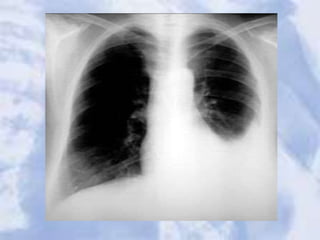

Pleural effusion: Note loss of left hemidiaphragm. Fluid drained

via thoracentesis